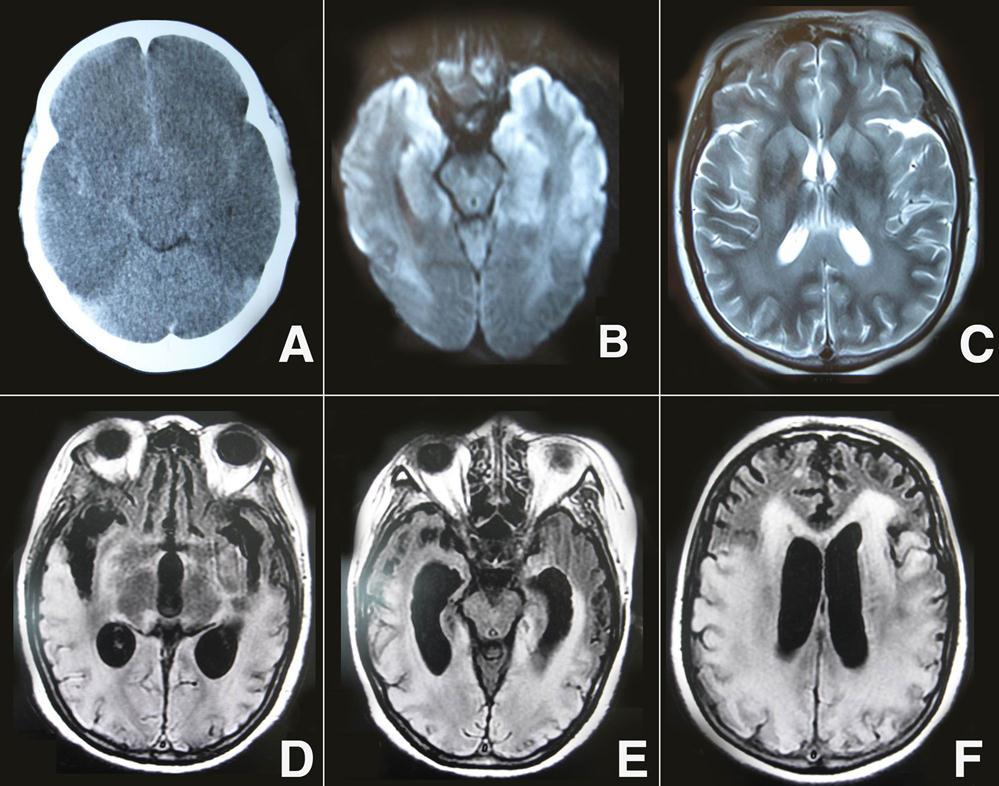

A 46-year-old woman was found in cardiorespiratory arrest after she had an out-of-hospital an suddenly drop atroke lasting about 27 min. She was successfully resuscitated and admitted to the intensive care unit.The etiopathogenesis of cardiac arrest was ventricular fibrillation for patient. On initial examination, her pupils were 2 mm in diameter and nonreactive to light, and there was unresponse to external stimulation, and the score on the Glasgow Coma Scale was 3(E1V1M1). On admition, initial head CT revealed no significant findings. On the three days after onset, a repeat noncontrast CT images showed a whole cerebral brain swelling, caudal transtentorial Herniation, and microhemorrhages in the intercerebral and subarachnoid (Figure 1A). Diffusion- weighted magnetic resonance imaging (DWI) performed on day 14, the patient showed extensive lesions of the bilateral middle, hippocampus and the gray matter of the frontal and temporal cortices (Figure 1 B). In addition, brain MRI T2-weighted imaging showed bilateral symmetric high signal intensity in the caudate, putamen, thalami, occipital, parietal cortices and subcortical white matter (Figure 1C). After 20 days, her neurological status was improved, the GCS scale was 8 (E4V1M3). she did not show any signs of conscious perception regarding the different types of stimulation, including pain. She had been in a vegetative state. On follow-up MRI 60 days later, Fluid-attenuation inversion recovery image (FLAIR) showed cortical, subcortical white matter, and periventricular white matter confluent hyperintense lesions in the bilateral temporal, parietal, and occipital regions, and enlarged ventricles (Figure 1D-F). After three months, she did not perform requested commands and displayed spastic palsy to a higher extent in the lower limbs. The GCS scale was 9 (E4V1M4), and she was declared a persistent vegetative state.

Figure 1.A) Brain CT showed a whole cerebral brain swelling, caudal transtentorial Herniation, and microhemorrhages in the intercerebral and subarachnoid; B) DWI showed extensive lesions of the bilateral middle, hippocampus and the gray matter of the frontal and temporal cortices; C) brain MRI T 2-weighted imaging showed bilateral symmetric high signal intensity in the caudate, putamen, thalami, occipital, parietal cortices and subcortical white matter; D-F) On follow-up MRI 60 days later, FLAIR showed cortical, subcortical white matter, and periventricular white matter confluent hyperintense lesions in the bilateral temporal, parietal, and occipital regions, and enlarged ventricles.